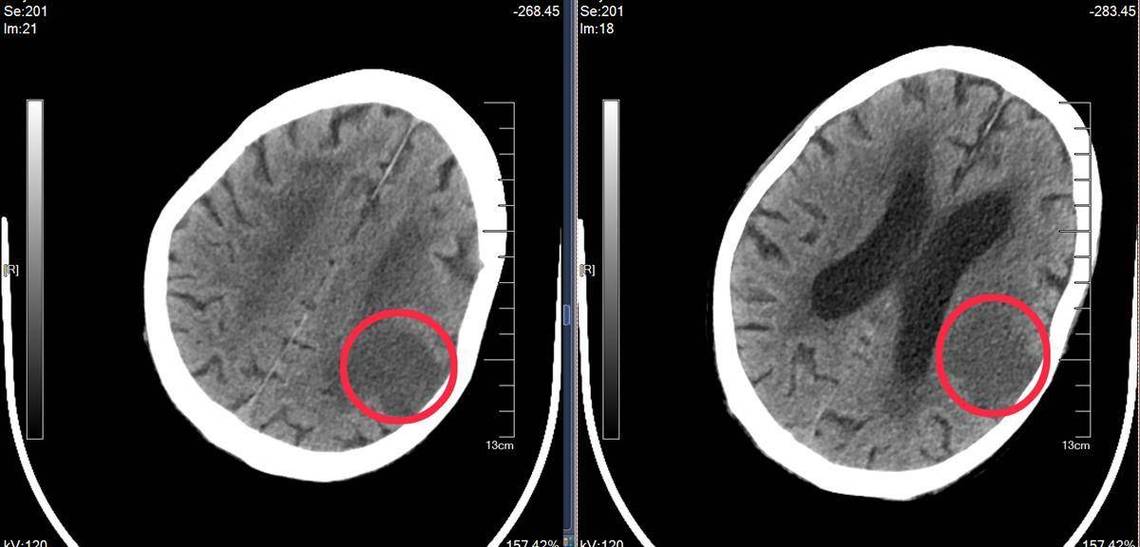

完善相关检查:

- 医生通常会建议做头颅MRI(磁共振),MRI对小的梗塞灶比CT更敏感,看得更清楚,能更好地评估脑小血管病的整体情况。